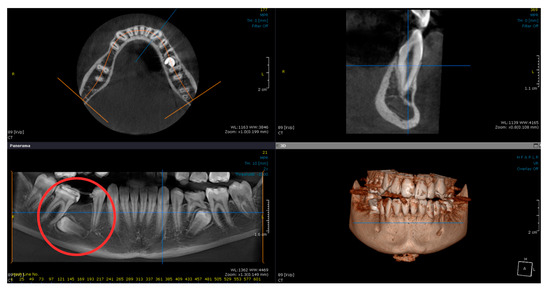

2.3. Treatment Progress

2.4. Treatment Outcome